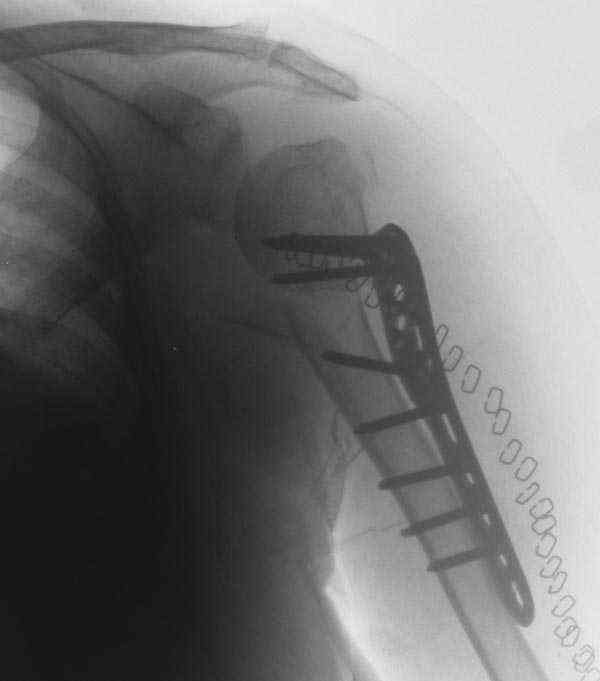

The reduction is not perfect. The patient is very small made, and it was

difficult to bring the plate proximally without impingement in abduction.

Pain relief after surgery was early and sustained.